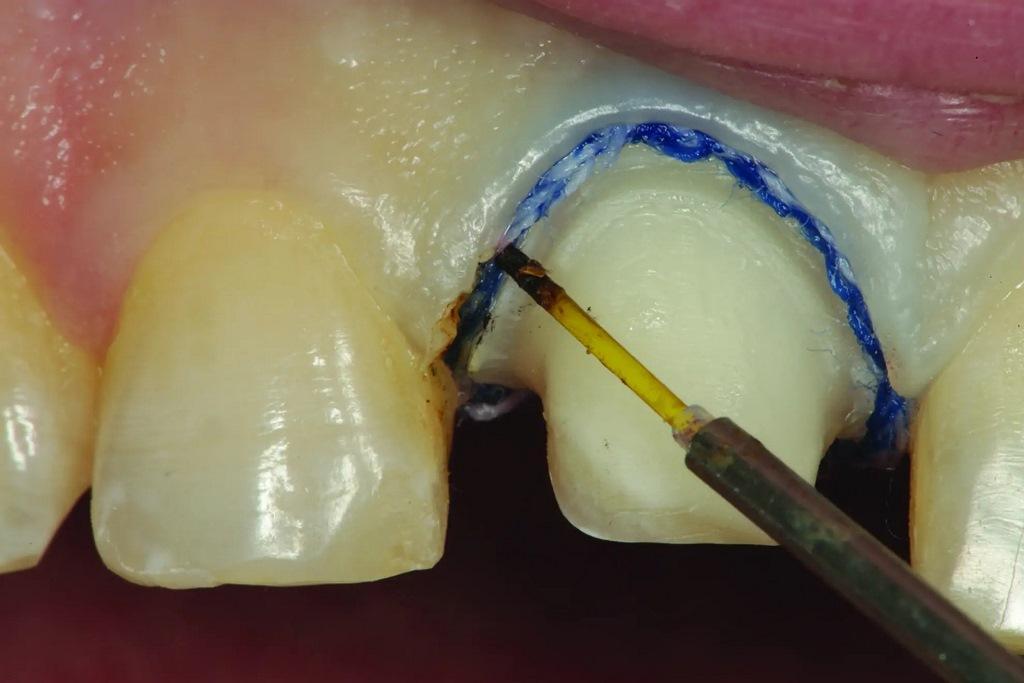

В данном случае, после установки ретракционной нити 1, в лицевой области препарирования образовался избыток ткани, который, возможно, препятствовал прохождению поддесневого оттискного материала. Сверхимпульсный диодный лазер (Gemini, Ultradent Products) использовался для тщательного удаления излишков ткани, прилегающей к нити, без повреждения нити (фото 12-13). Ретракционная нить была полностью видимой перед удалением, что обеспечивало беспрепятственный доступ легкого оттискного материала в отведенную область.

Фото 12: С помощью сверхимпульсного диодного лазера удаляют излишки ткани, надрезая верхнюю нить.